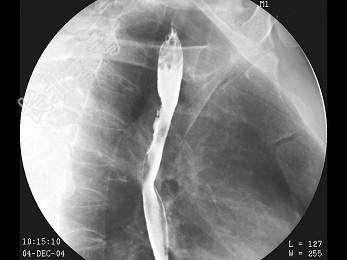

- 多项选择题男,55岁, 上腹饱胀不适2月,结合图像, 最可能的诊断是 ( )

B、食管癌

C、食管静脉曲张